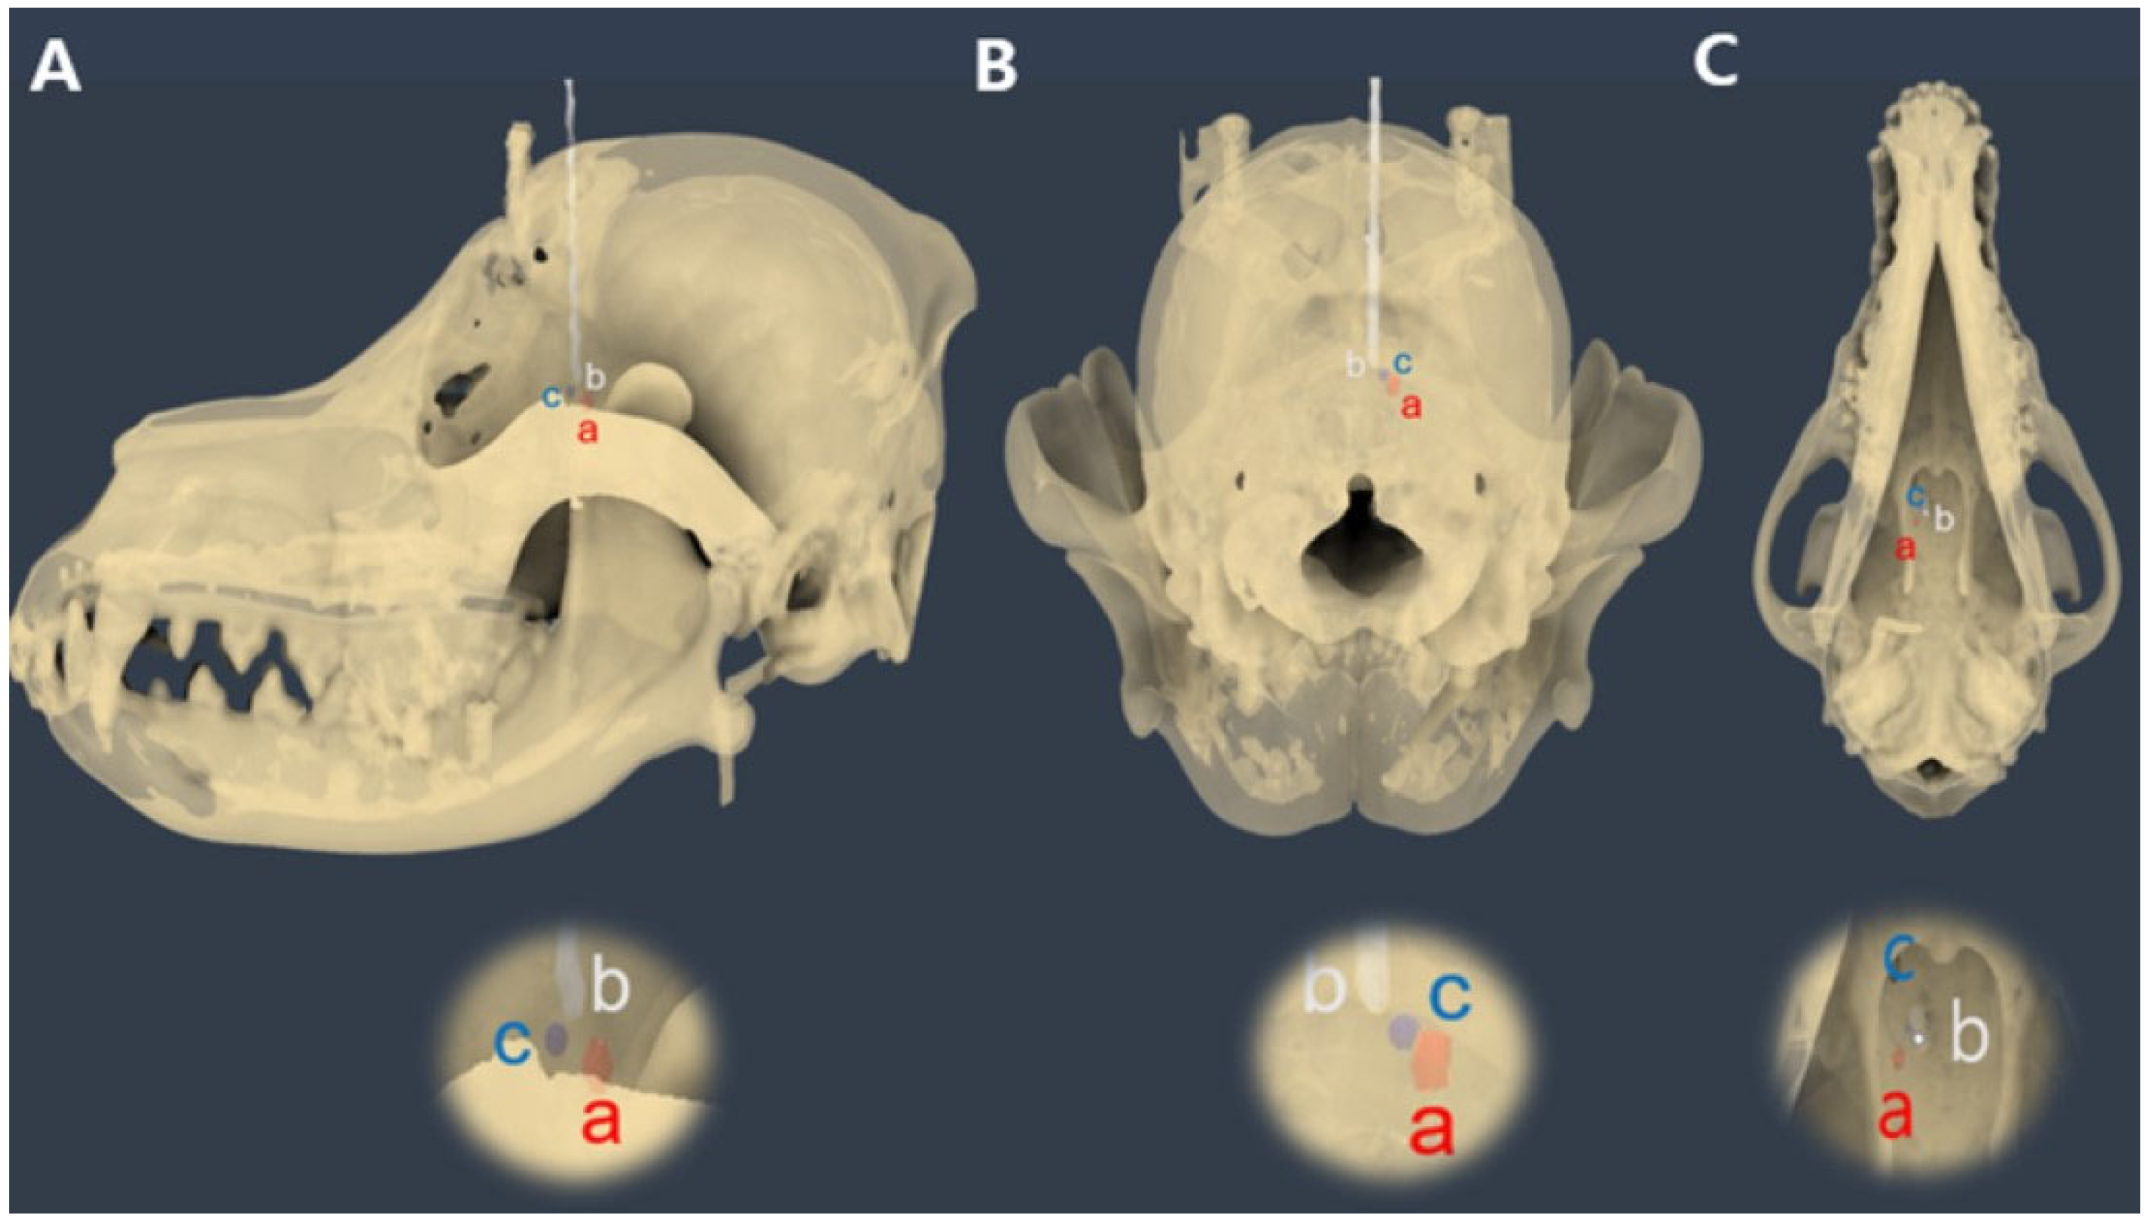

Intraoperative CT images were transmitted to Mimics Medical software (version 21.0; Materialize NV, Leuven, Belgium) for stereolithography (STL) file generation, similar to preoperative imaging. Segmentation was performed using appropriate thresholding techniques to isolate the skull, 3D guides, spinal needle, and tumor model. Subsequently, the STL files were transferred to computer-aided design software (Fusion 360, Autodesk, San Rafael, CA, USA). Using Fusion 360 software (Autodesk, San Francisco, CA, USA), preoperative and intraoperative STL files were fused to assess the needle placement errors. The preoperative skull was aligned with the intraoperative skull, and the endpoints of the spinal needle tip, the center point of the target ROI, and the center point of the tumor model were marked. The distance between the needle tip point and center point of the target ROI was measured. The relative orientation of the spinal needle tip point was determined using the sagittal, dorsal, and transverse views. The distance between the needle tip point and the center point of the tumor model was measured, and the positional relationships were assessed (Figure 8).

The entry point was defined as the point at which the needle passed through the most proximal plane of the preoperative needle guide, and the endpoint of the needle was defined as the exit point. Displacement was measured from an actual reference point. When determining the relative positions of all points, the rostral direction was designated as positive (+), the caudal direction as negative (−), the lateral value as positive (+), and the medial value as negative (−) (Figure 9).

Figure 8. Calculation of needle placement error in the fronto-olfactory lobe after inserting a spinal needle, as assessed by the 3D volume-rendering method. (A) The center of the tumor model was designated as point ‘a’, the end of the spinal needle as point ‘b’, and the center of the ROI was designated as point ‘c’. (B) The spatial relationships of the three points in the transverse view. (C) The spatial relationships of the three points in the axial view. The distance between each point can be measured using the measurement function.

Figure 9. Evaluation of the needle trajectory. (A) Overall view of the needle trajectory. (B,C) Set the midpoint (a) of the most proximal surface of the preoperatively planned needle insertion unit and then create a circle with a diameter of 1–5 mm. Next, establish the actual center (b) where the spinal needle passes through this surface and determine the needle endpoint (c). Finally, assess the positional relationship of these points on the dorsal plane.